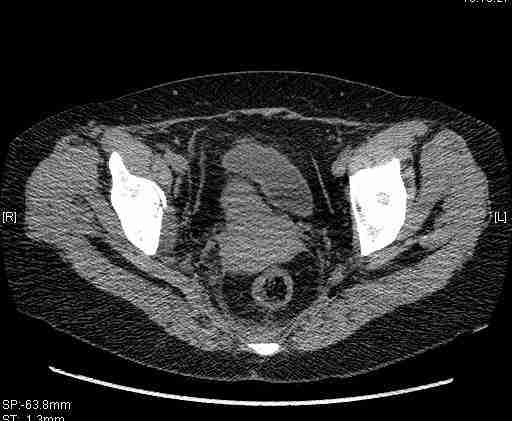

Женщина,58 лет, после ДТП 6 суток. Первично повреждение расценено как переломы ветвей лонной кости. После подтверждения повреждения вертлужной впадины,как чаще всего случается, вопрос встал о тактике. БОльшинство за консерватиное лечение.К сожалению кт у нас "во время" сломался. Прилагаю стандартные снимки вертлужки. У меня следующие вопросы к коллегам:1. Правильно ли рассценивать это повреждение как Т-образный перелом вертлужнй впадины?2. Можно ли добиться анатомической репозиции поверхности вертлужной впадины скелетным вытяжением в данном случае, если нет, что будет этому препятствовать?3. Если смещение останется таким как сейчас, через какое время появится необходимость эндопротезирования (по вашему опыту)?Спасибо.

Удалось сегодня вывести пациентку в соседнюю больницу, где есть кт. Срезы сделаны только горизонтальные.

|

Приветствую,Антон.Рункова рядом нет,но после полученных данных КТ,обсуждали совместно.Итог обсуждения-развернутый ответ дать не получится,т.к.срезы выбраны не информативные.Если ориентироваться на данные 3D,то ,ИМХО,можно лечить на вытяжении.